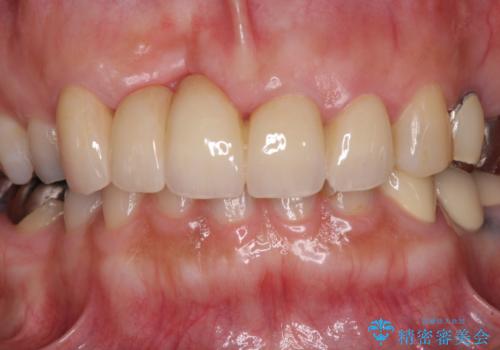

仮歯に置き換えた時点で見た目が大きく改善され、人目を気にすることがなくなりました。

オールセラミッククラウンは、本物の歯のような外観となり、患者様には大変満足していただけました。